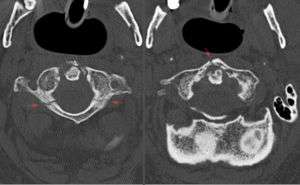

Axial CT scan of Jefferson fracture

- Fracture of the anteterior and posterior arches[1]

- Due to axial loading transmitted through occipital condyles to the lateral masses